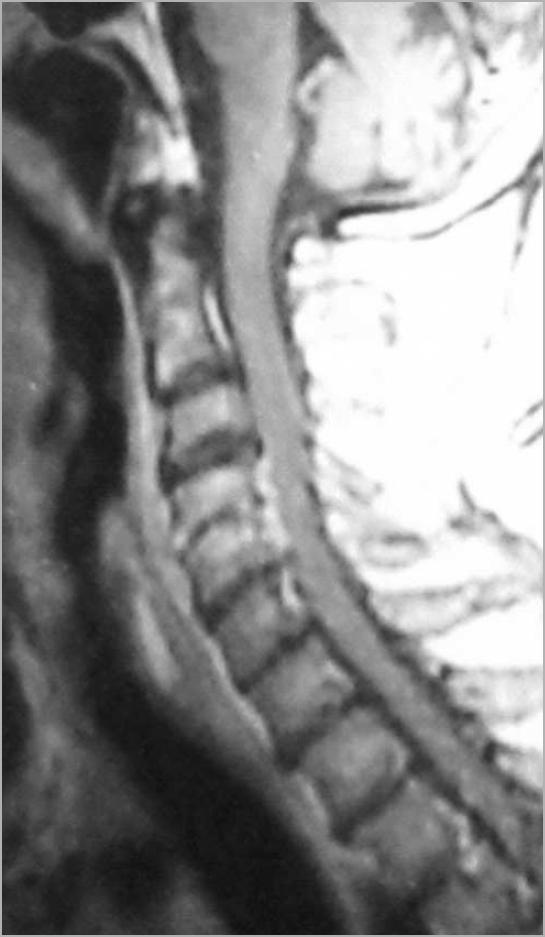

Despite advances in neuroimaging and neurosurgical treatment modalities, spinal epidural abscess remains a challenging problem. Early diagnosis is often difficult and treatment is always delayed. Spinal epidural abscess usually develops in patients with predisposing factors such as IV drug abuse, senillity, diabetes mellitus, spinal attempts, alcoholism, immunosuppression, liver diseases and catheterizations. It is rarely seen in cervical region. A successful treatment is only possible with early diagnosis and accurate surgical and medical treatment. Optimal management is unclear and morbidity and mortality are significant. We present two adult haemodialysis patients with end-stage renal insufficiency who developed cervical epidural abscess following central venous catheter placement. Early surgical intervention is mandatory in cases those have progressive neurological deficit and spinal deformity, and this is also increases the success rate of medical therapy.

尽管神经影像学和神经外科治疗方法取得了进展,但脊髓硬膜外脓肿仍然是一个具有挑战性的问题。早期诊断通常很困难,治疗总是会被延误。脊髓硬膜外脓肿通常发生在有易患因素的患者中,如静脉内药物滥用、衰老、糖尿病、脊柱尝试、酗酒、免疫抑制、肝病和导管插入术。它在颈椎区域很少见。只有早期诊断和准确的手术及药物治疗才能取得成功。最佳治疗方法尚不清楚,发病率和死亡率都很高。我们介绍了 2 例终末期肾功能不全的血液透析成年患者,他们在中心静脉置管后发生了颈椎硬膜外脓肿。对于那些有进行性神经功能缺损和脊柱畸形的病例,早期手术干预是必需的,这也增加了药物治疗的成功率。